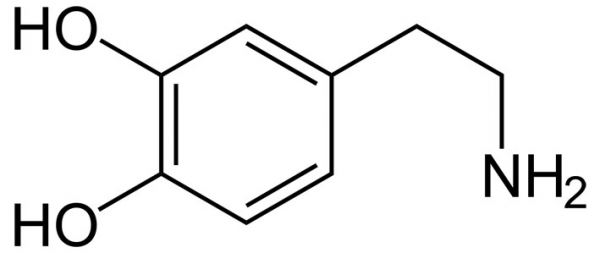

bu da dopamin. yine halkasal yapıya dikkat ediniz.

evet... bu hormonların hepsi tiroksin aminoasitinden sentezlenir. çünkü tiroksin aminoasitinden bu halkasal yapı alınarak başka moleküller ile birleştirilip bu hormonlar oluşturulur. bu halkasal yapılar, benzen, fenil- fenol ve benzeri yapılar şeker, yağ gibi besinlerde bulunmaz. yalnız tirozin ve fenilalanin aminoasitinden elde edilebilir. dışarıdan almak zorundasınız, zira vücudumuzun bu molekülleri sentezleme yetenekleri yoktur-sınırlıdır. ve bu aminoasitler olmadan bu adı geçen hormonları sentezleyemezsiniz. bu da vücudunuzun genel işleyişini bozarak ciddi metabolik hastalıklara yol açacaktır.